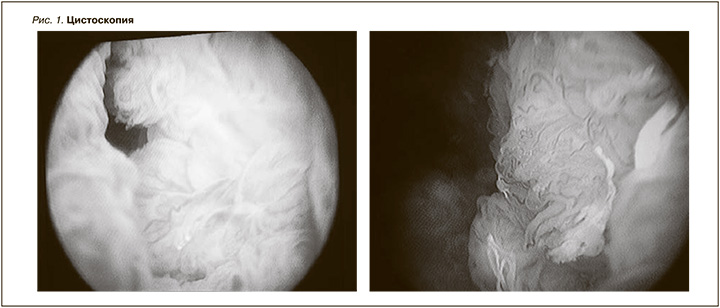

Выполнена попытка трансуретральной резекции с гемостазом и биопсией МП: уретра свободна, проходима для тубуса цистоскопа № 19. Слизистая оболочка уретры и шейки розовая, инъецирована сосудами, без признаков воспаления. Семенной бугорок визуализирон. В простатическом отделе уретры визуализируется ворсинчатое образование, кровоточит при контакте с цистоскопом. Пройти инструментом в МП из-за данного образования не возможно (рис. 1). Взята щипковая биопсия.